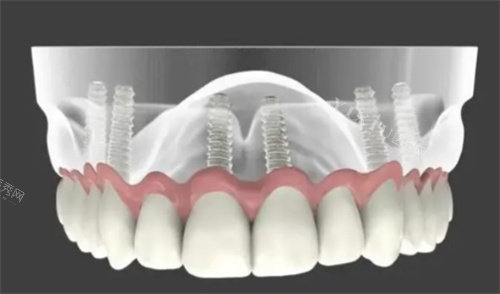

1. All-on-6种植技术

All-on-6是一种通过6颗种植体支撑全口牙冠的种植方案,适合骨量中等或对咬合力要求较高的患者。2025年,All-on-6种植技术的价格区间为12万-17万元。这种方案的优点是创伤小、改善快,且能够提供良好的咀嚼功能和美观结果。